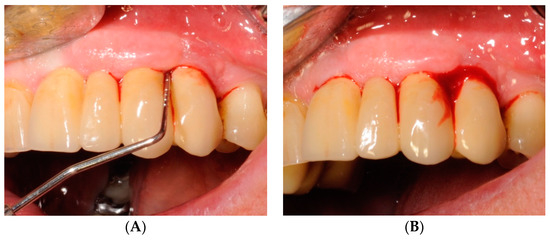

2.1. Demographics

2.2. Clinical Outcomes

4. Materials and Methods

4.1. Study Design

4.2. Soft Tissues Assessment

4.4. Study Protocol and Treatment

4.5. Test Substances and Administration